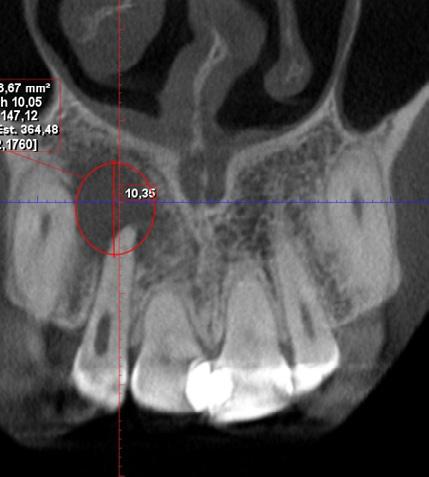

Tratamiento combinado de un quiste radicular de larga data: A propósito de un caso clínico

Combined treatment of a long-standing radicular cyst: A clinical case report

Javier BorisAdrián Burgos, Johanna Valentina Virreyra Bloomfield..........................................................133-142